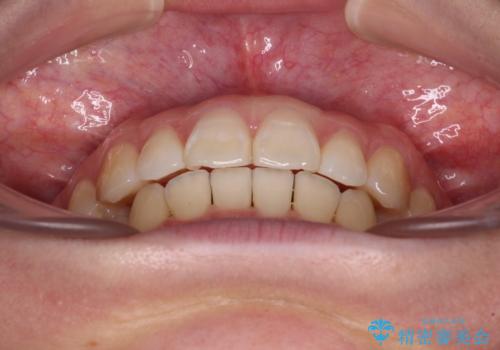

咬合高径の挙上により上顎前歯の突出感も改善することができ、整った口元となりました。